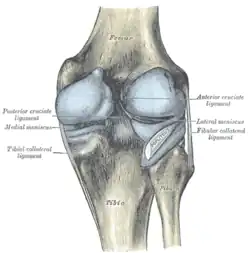

La rodilla está sustentada por fuertes ligamentos que impiden que sufra una luxación, siendo los más importantes el ligamento lateral externo, el ligamento lateral interno, el ligamento cruzado anterior y el ligamento cruzado posterior.[4]

Ligamentos

La rodilla esta sustentada por varios ligamentos que le dan estabilidad y evitan movimientos excesivos. Los ligamentos que están en el interior de la cápsula articular se llaman intraarticulares o intracapsulares, entre los que se encuentra el ligamento cruzado anterior y el ligamento cruzado posterior. Por otra parte los ligamentos que están por fuera de la cápsula articular se llaman extrarticulares o extracapsulares como el ligamento lateral interno y el ligamento lateral externo.[8][9]

Intraarticulares

- Ligamento cruzado anterior (LCA).

- Ligamento cruzado posterior (LCP).